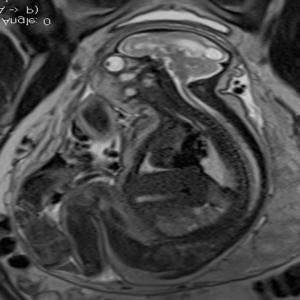

In a third study, ultrasound and fetal MRI were performed on pregnant patients with Zika virus infection at different gestational ages. Once the babies were born, they underwent ultrasound, CT and MRI. The researchers then created 3-D virtual and physical models of the skulls. More than half the babies had microcephaly, brain calcifications and loss of brain tissue volume, along with other structural changes.

"The emergence of Zika virus in the Americas has coincided with increased reports of babies born with microcephaly," said study author Heron Werner Jr., M.D., Ph.D., from the Department of Radiology at Clínica de Diagnóstico por Imagem. "An early diagnosis may help in treating these babies after birth. Moreover, the knowledge of abnormalities present in the central nervous system may give hints about the pathophysiology of the disease."